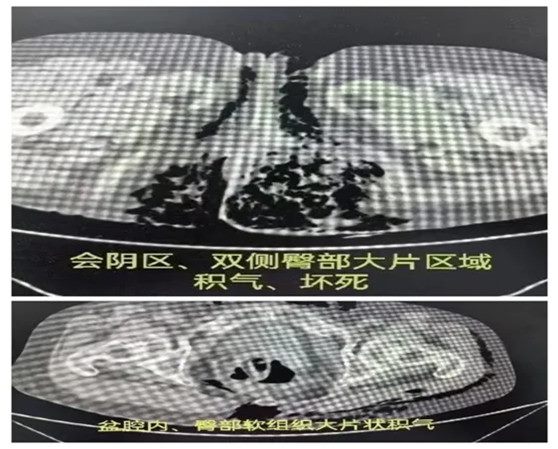

一位老年女性患者因“突发胸闷6小时”入住郑大五附院心血管内科,在进行血管扩张和改善循环治疗后,胸闷症状未得到有效缓解,同时感染性指标显著升高。患者自诉肛周疼痛不适,急诊会诊后,检查发现一侧臀部明显波动感,另一侧臀部触诊有“握雪感”,考虑为肛周脓肿合并坏死性筋膜炎。CT检查显示直肠周围结构紊乱,盆腔内、双侧臀部、会阴部及下腹部软组织内多发积气,进一步证实了肛周严重感染合并坏死性筋膜炎,且感染正在迅速蔓延,伴有呼吸困难和血压不稳定,疑似脓毒症休克。根据患者的紧急病情,晚间及时进行急诊手术。术中发现直肠吻合口瘘引发的肛周、会阴部及下腹壁多部位软组织感染。通过广泛切开引流成功控制了感染源,缓解了脓毒症休克,术后患者病情平稳出院。

难点总结:本病例的难点在于直肠吻合口瘘引发的严重感染,导致坏死性筋膜炎及脓毒症休克的发生。由于感染蔓延迅速,且患者存在多脏器功能障碍,急诊手术的时机至关重要。

推荐理由:在于通过及时且精准的手术干预,成功控制了感染源,并迅速改善了脓毒症休克,避免了患者的病情恶化。此次病例展示了直肠吻合口瘘引发的并发症及其快速蔓延的危险性,也凸显了急诊手术和多学科协作在抢救生命中的重要作用。